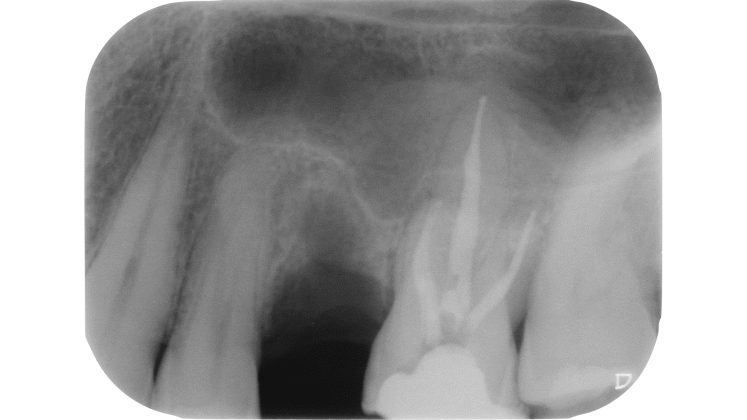

Devono essere valutate con molta attenzione la posizione dell’elemento in arcata e la sua inclinazione (Figure 6-7), l’entità e la posizione del processo carioso se presente, gli eventuali restauri posizionati sul dente e i rapporti con il parodonto: tutte queste considerazioni permetteranno al clinico di capire innanzitutto la mantenibilità e la possibilità di isolare mediante diga di gomma il dente. L’interpretazione degli esami radiografici consentirà inoltre di valutare alcuni parametri preoperatori di notevole importanza:

Un’attenta analisi di questi dati clinici e radiografici consentirà al clinico di ridurre notevolmente il rischio di errori grossolani in questa delicata fase del trattamento.